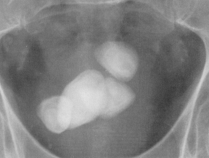

Litiaza vezicii urinare poate fi primara sau cu calculi migrati din caile urinare superioare. Cea primara apare pe fondul stazei urinare vezicale din adenomul periuretral si sunt mari, rotund-ovalari, cu contur net, regulat. Exista întotdeauna si alte leziuni asociate (cistita hipertrofica, diverticuli vezicali, amprenta inferioara prostatica a fundului vezical, uretere pelvine alungite, deformate "în cârlig de undita").